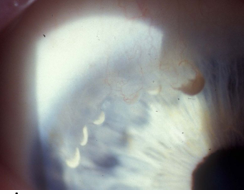

Terrien’s Marginal Degeneration

Uncommon.

Most cases are male, usually over 40.

Bilateral, slow progression.

Signs/Symptoms

Superior nasal (usual) thinning of the peripheral corneal stroma with an intact epithelium.

Upper corneal punctate stromal opacities, mild vascularization, gutter formation, circumferential spread.

Vision loss from irregular astigmatism.

Typically patients are asymptomatic.